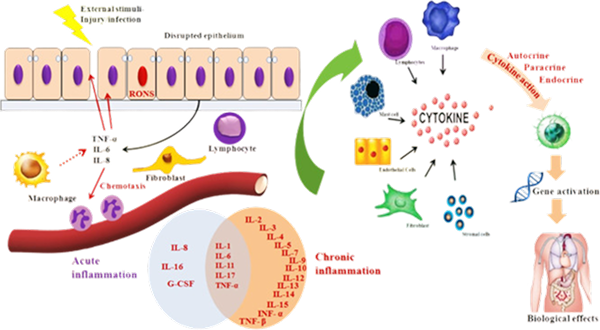

What is inflammation & is all inflammation bad?

Cellular inflammation is a type of inflammation that occurs below the level of pain. It’s a vital defense mechanism that’s part of the immune system’s response to harmful stimuli, such as damaged cells, pathogens, toxic compounds, or irradiation. The purpose of inflammation is to remove harmful stimuli and start the healing process. Not all inflammation is “BAD”. Inflammation is required for transformation & to initiate the body’s healing process. If the immune system is not equipped (The adaptive immune system) to respond to reducing inflammation, chronic cellular dysfunction can occur.

Inflammation is always followed by recovery & restoration. If the balance of inflammation to recovery is off, this puts one at risk for chronic inflammation. Chronic inflammation is one of the root causes of chronic cellular dysfunction, which can manifest itself asInflammation is always followed by recovery & restoration. If the balance of inflammation to recovery is off, this puts one at risk for chronic inflammation. Chronic inflammation is one of the root causes of chronic cellular dysfunction, which can manifest itself as:

Growth factors, cytokines, and extracellular vesicles (exosomes): These substances may help reduce cellular inflammation and pain, and speed up the healing of musculoskeletal injuries